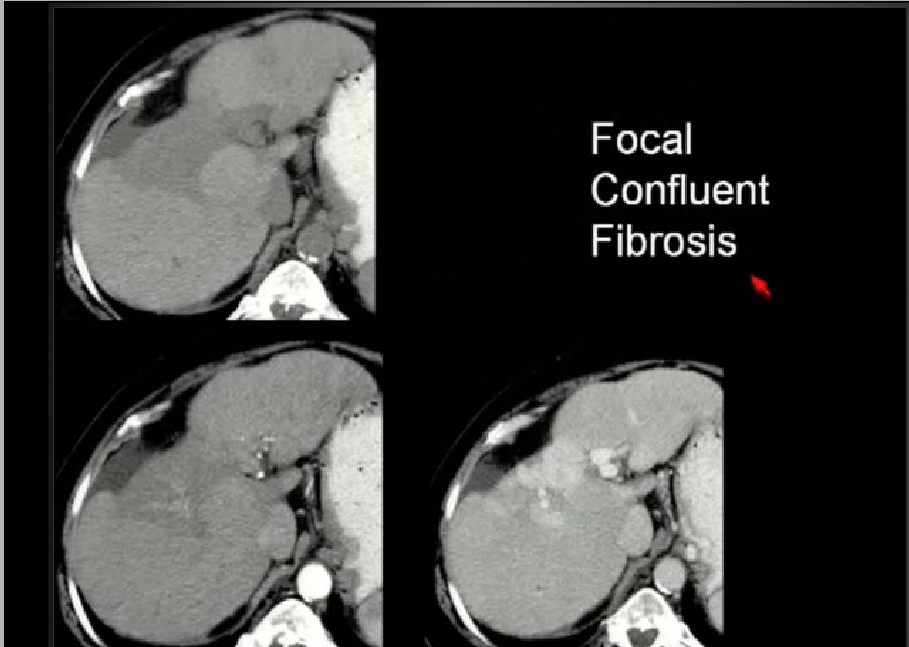

HCC and dysplastic nodule

focal confluent fibrosis가 다른 fibrosis와 마찬가지로 delayed phase에서 조영증강된다.